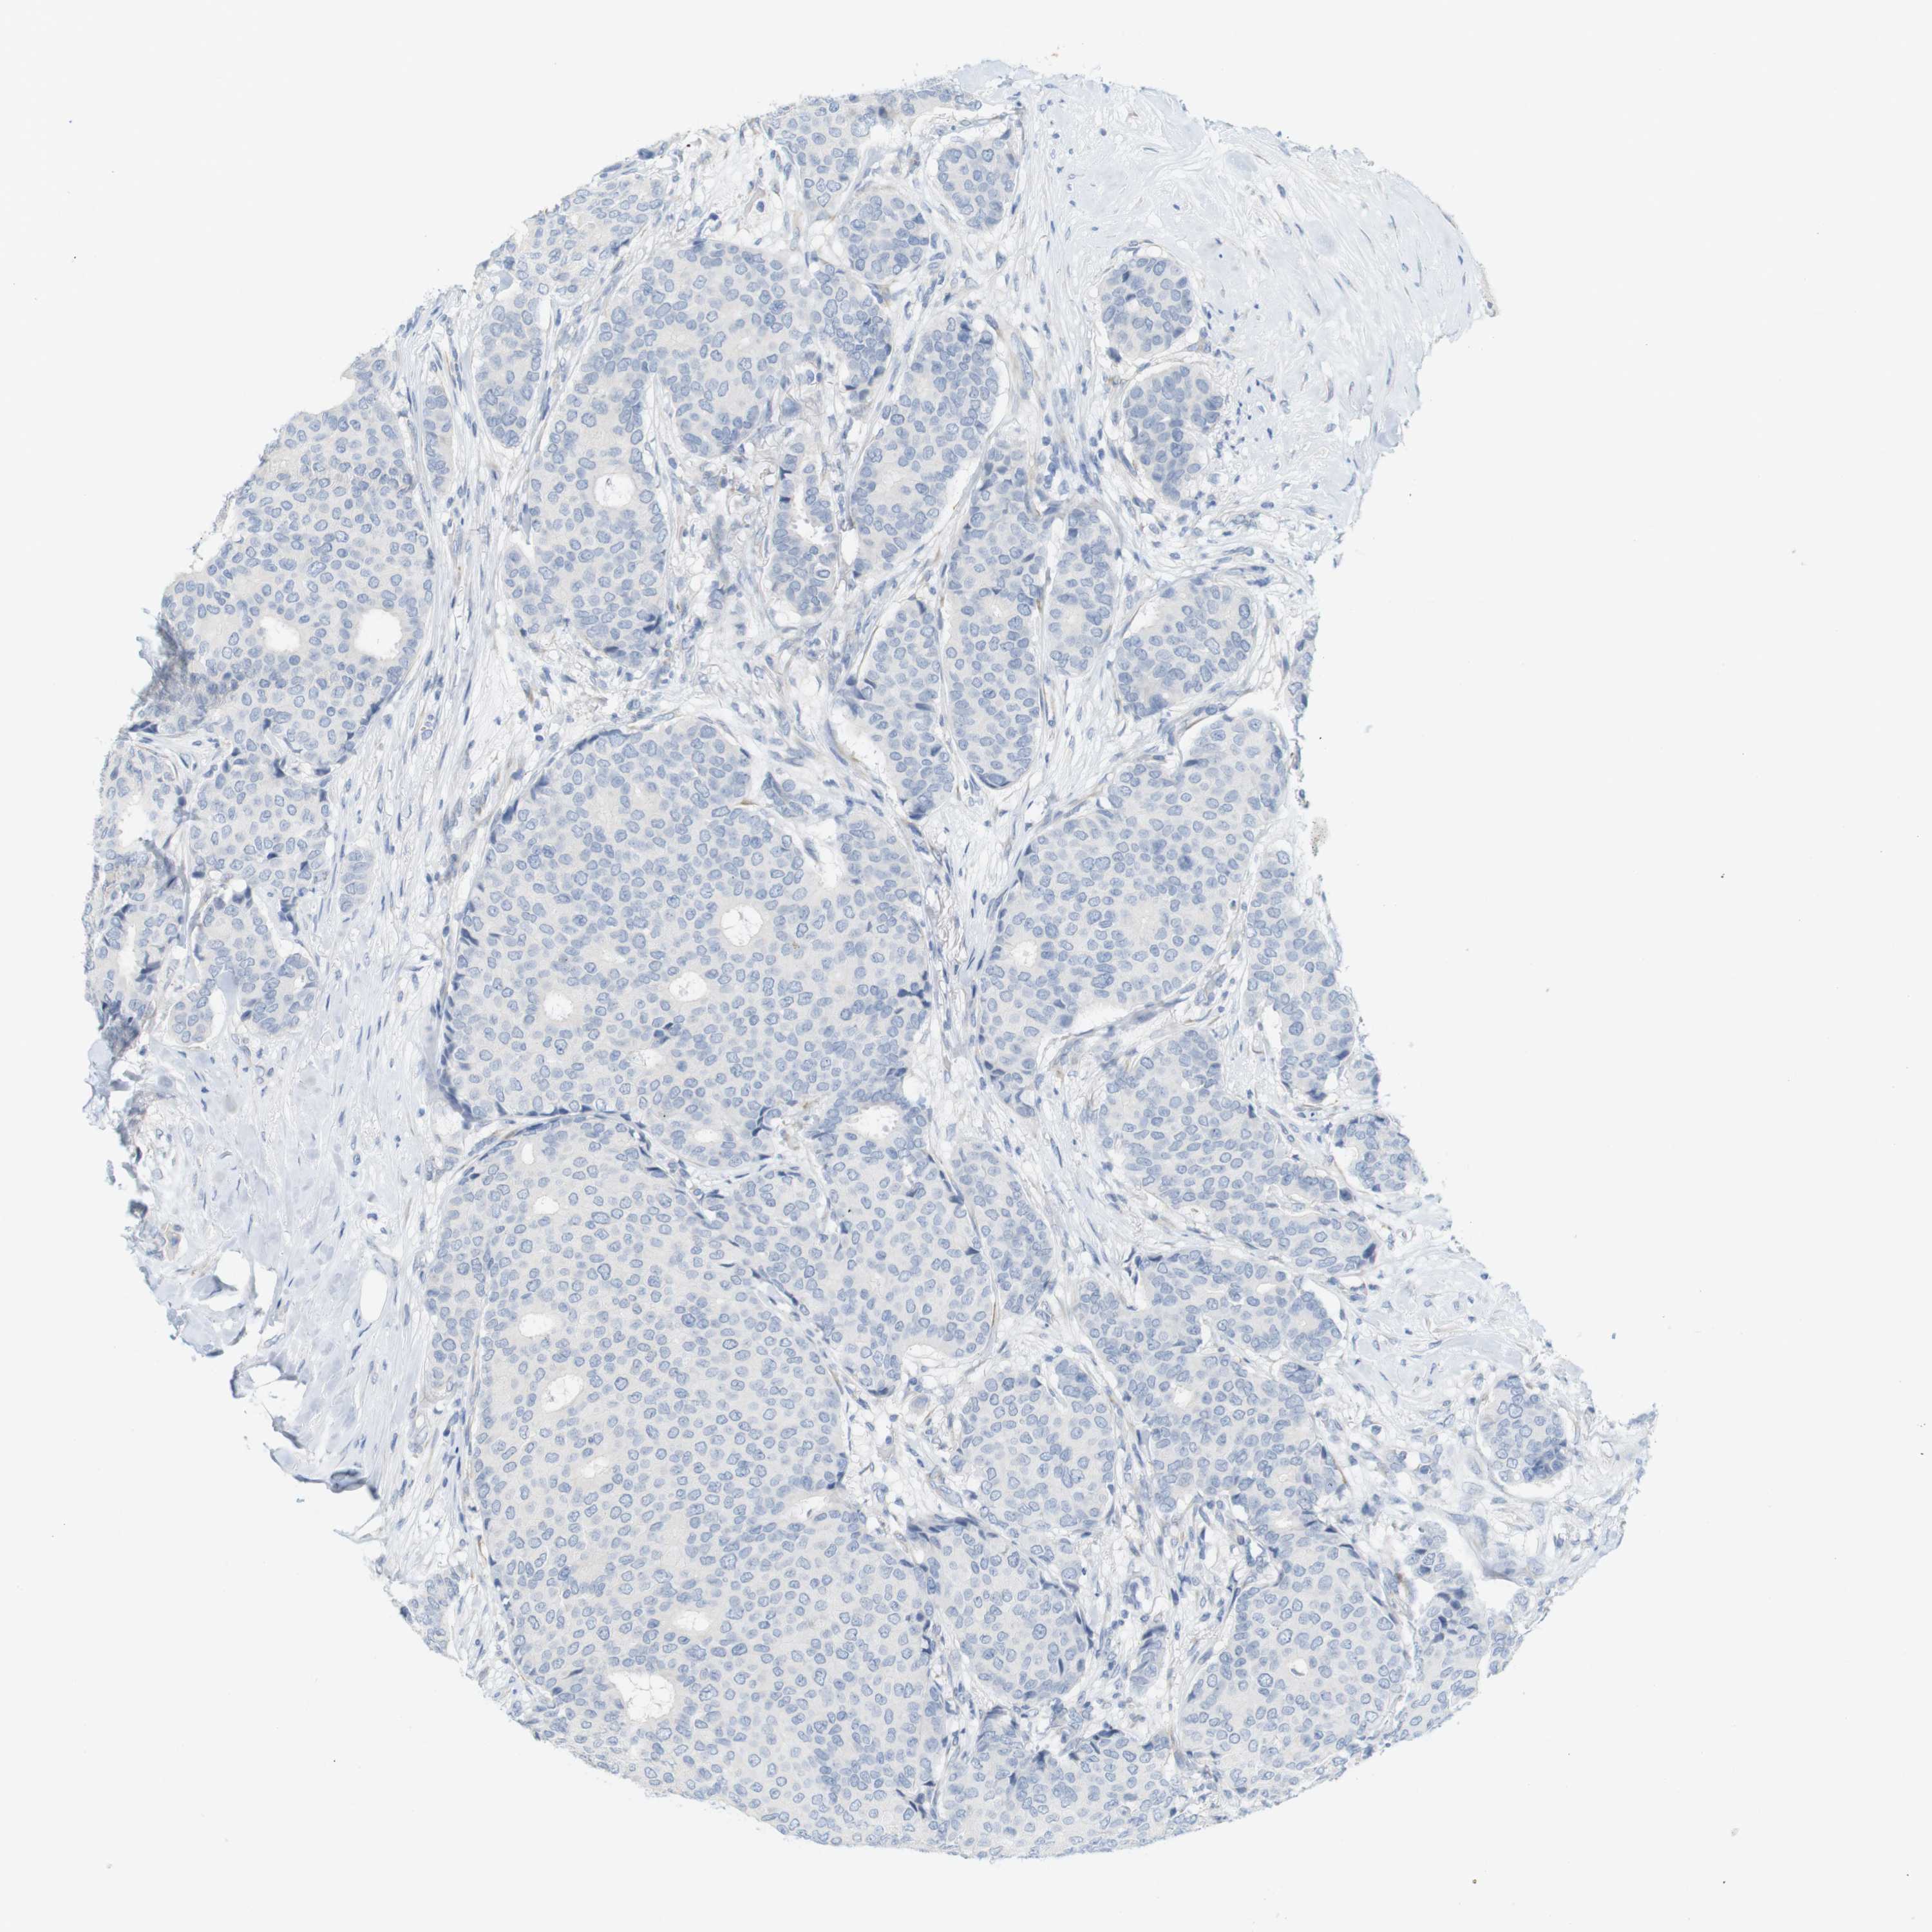

CANCER BREAST CANCER Show tissue menu

BRCA TCGA BRCA VALIDATION PROTEIN EXPRESSION

ANTIBODIES

AND

VALIDATION